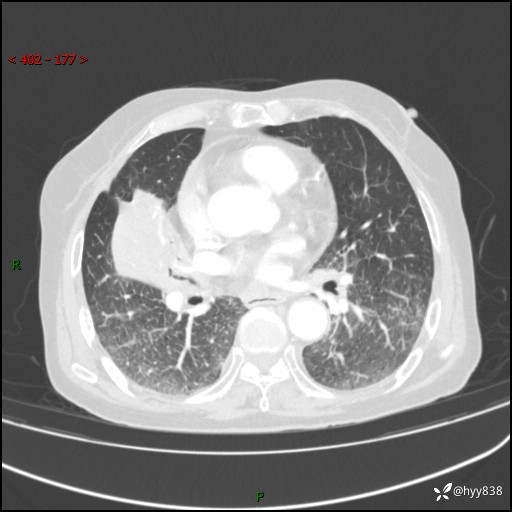

胸部CT增强(外院平扫)